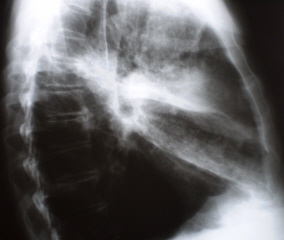

На линейных томограммах, произведенных в прямой проекции (иллюстрации 3, 4) участок сниженной прозрачности легочной ткани довольно однородной структуры. По верхнему контуру дифференцируются «мелкие линейные структуры», направленные каудально. Корень правого лёгкого раздельно не дифференцируется, на воне его отдельные очаговые уплотнения. На всем протяжении легочных полей дифференцируются отдельные очаговые тени малой и средней интенсивности, преимущественно в средних и нижних отделах легочных полей, хорошо определяющиеся в латеральных отделах.